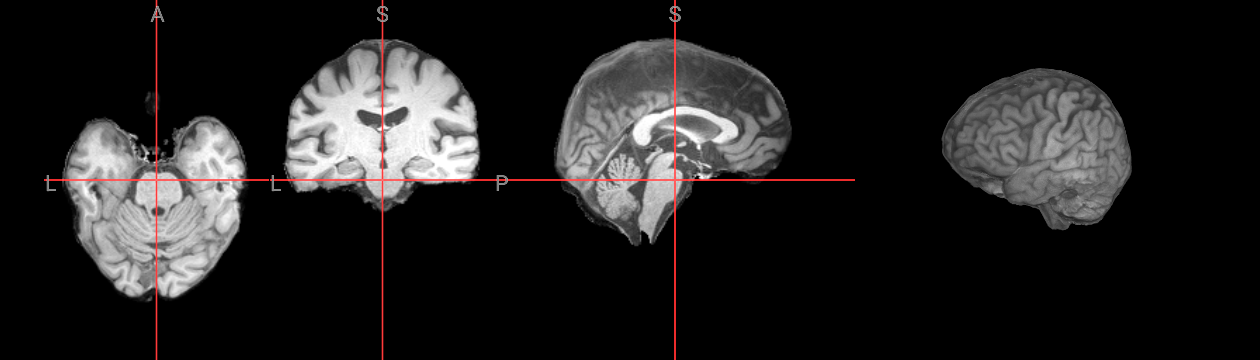

stderr 2025-11-10T00:50:59.619948:*+ WARNING: If you are performing spatial transformations on an oblique dset,

251110-00:50:59,620 nipype.interface INFO:

stderr 2025-11-10T00:50:59.619948: such as ds001226/sub-CON02/ses-preop/anat/sub-CON02_ses-preop_T1w.nii.gz,

251110-00:50:59,621 nipype.interface INFO: